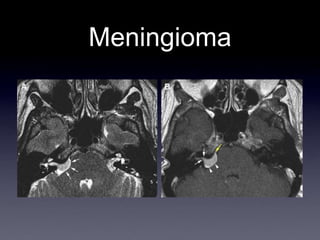

Meningioma

Meningioma del APC